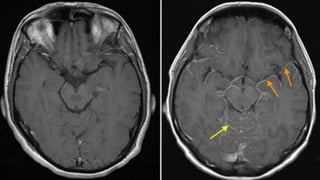

T1 contrast

• T1 contrast • T1 contrast

• Vessels -hyperintense